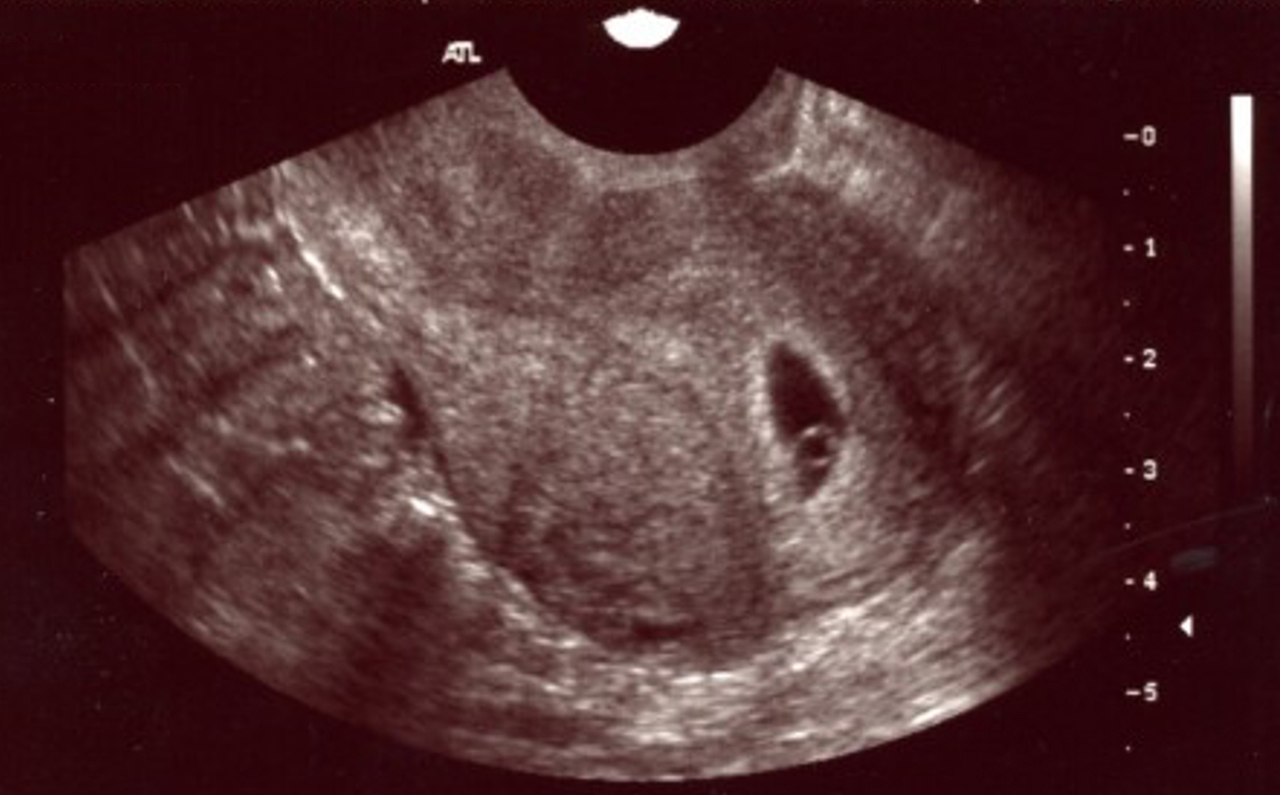

Samuel Khiat, La Revue du Praticien Echographie précoce en début de grossesse : grossesse intra-utérine.